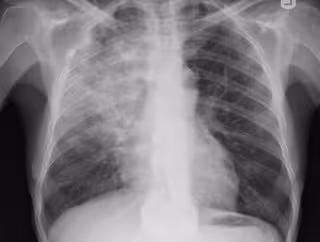

Neumonía, pulmonía, radiografía pulmones

FLICKR/YALE ROSEN